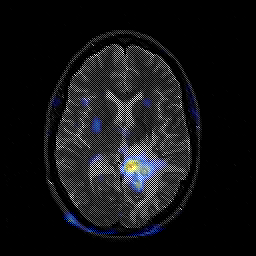

Glioblastoma multiforme overlay -- Slice #29

[Home][Help][Clinical][Tour 1][Tour 2][Tour 3] Slice 29